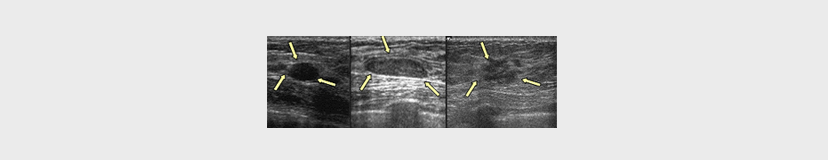

유방 초음파

유방 초음파 검사를 하는 경우

1 멍울(=혹)이 만져질 때

2 유방 촬영술에서 이상 소견이 보일 때

3 치밀 유방일 경우의 보조검사

저희 리앤아이 유방센터에서는 국내 유수 대학병원에서 사용하는 것과 동종의 장비를 사용하여 진단의 정확도를 높이고 있습니다.

2 유방에 있는 혹(=종양 또는 결절)을 발견하고 그 성상을 예측하는 것이 유방 촬영술보다 정확합니다.